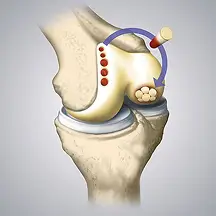

Cartilage is a smooth, resilient tissue that cushions and protects the ends of bones within a joint, allowing for frictionless movement and effective shock absorption. Despite its essential role in joint function, cartilage has a limited ability to heal on its own after injury. This is where the advanced cartilage repair and restoration techniques offered at Orthopaedics & Rehabilitation Excellence of Miami play a vital role in supporting joint health and recovery.

Our center offers advanced treatment options focused on repairing damaged cartilage, addressing the underlying cause of joint issues rather than simply managing symptoms. Below are some of the innovative cartilage repair and restoration procedures we offer.